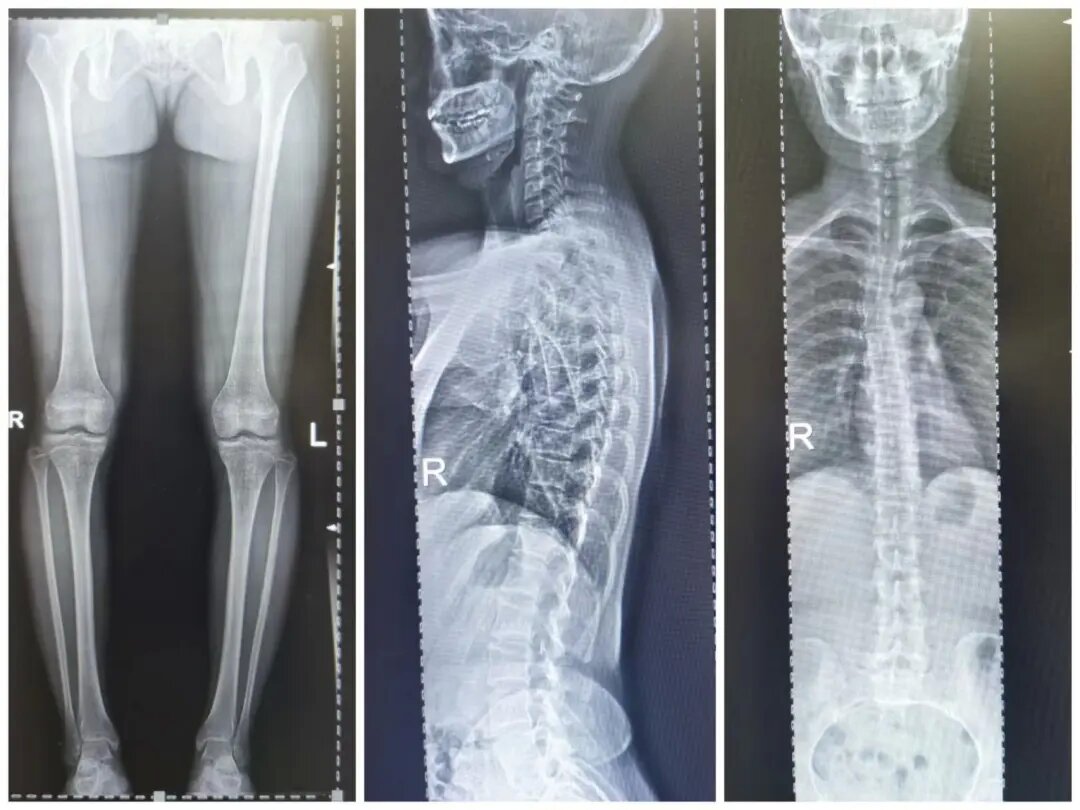

四、脊柱全长摄影及双下肢全长摄影

对脊柱侧弯、髋关节置换、膝关节置换给予全面、直观的影像资料。